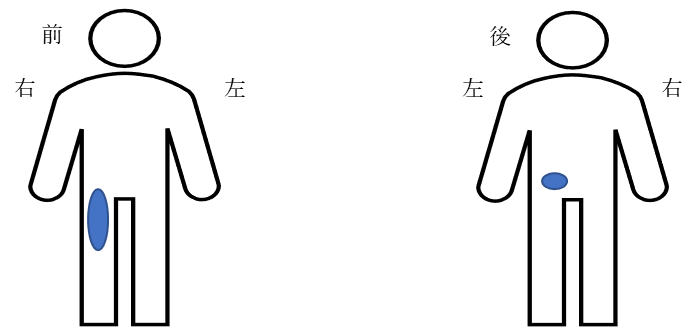

主な痛みの部分-腰、右下肢